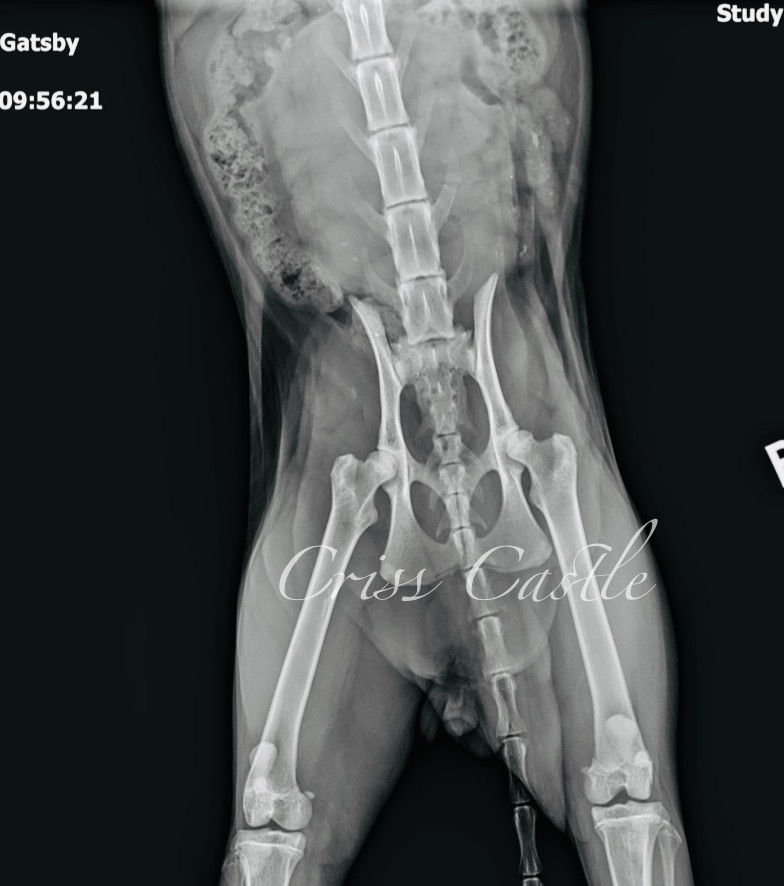

Gatsby